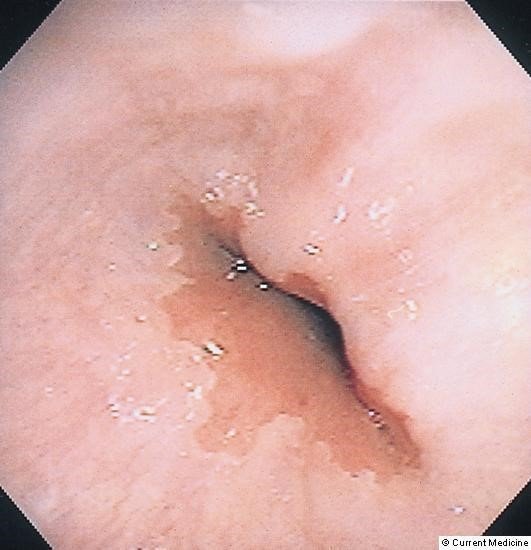

Diaqnozun dəiqiləşdirilməsi üçün kontrastlı Rentgenoloji müayinələr, KT və çox ehtiyatla endoskopiya edilir.

- Endoskopiya - divertikulun perforasiyası təhlükəsinə görə çox ehtiyatla aparılmalıdır.

- Endoskopiya - divertikulun perforasiyası təhlükəsinə görə çox ehtiyatla aparılmalıdır. QB-nun xəstəliklərinin və paraezofageal yırtıqların diferensiasiyası üçün mühümdür.